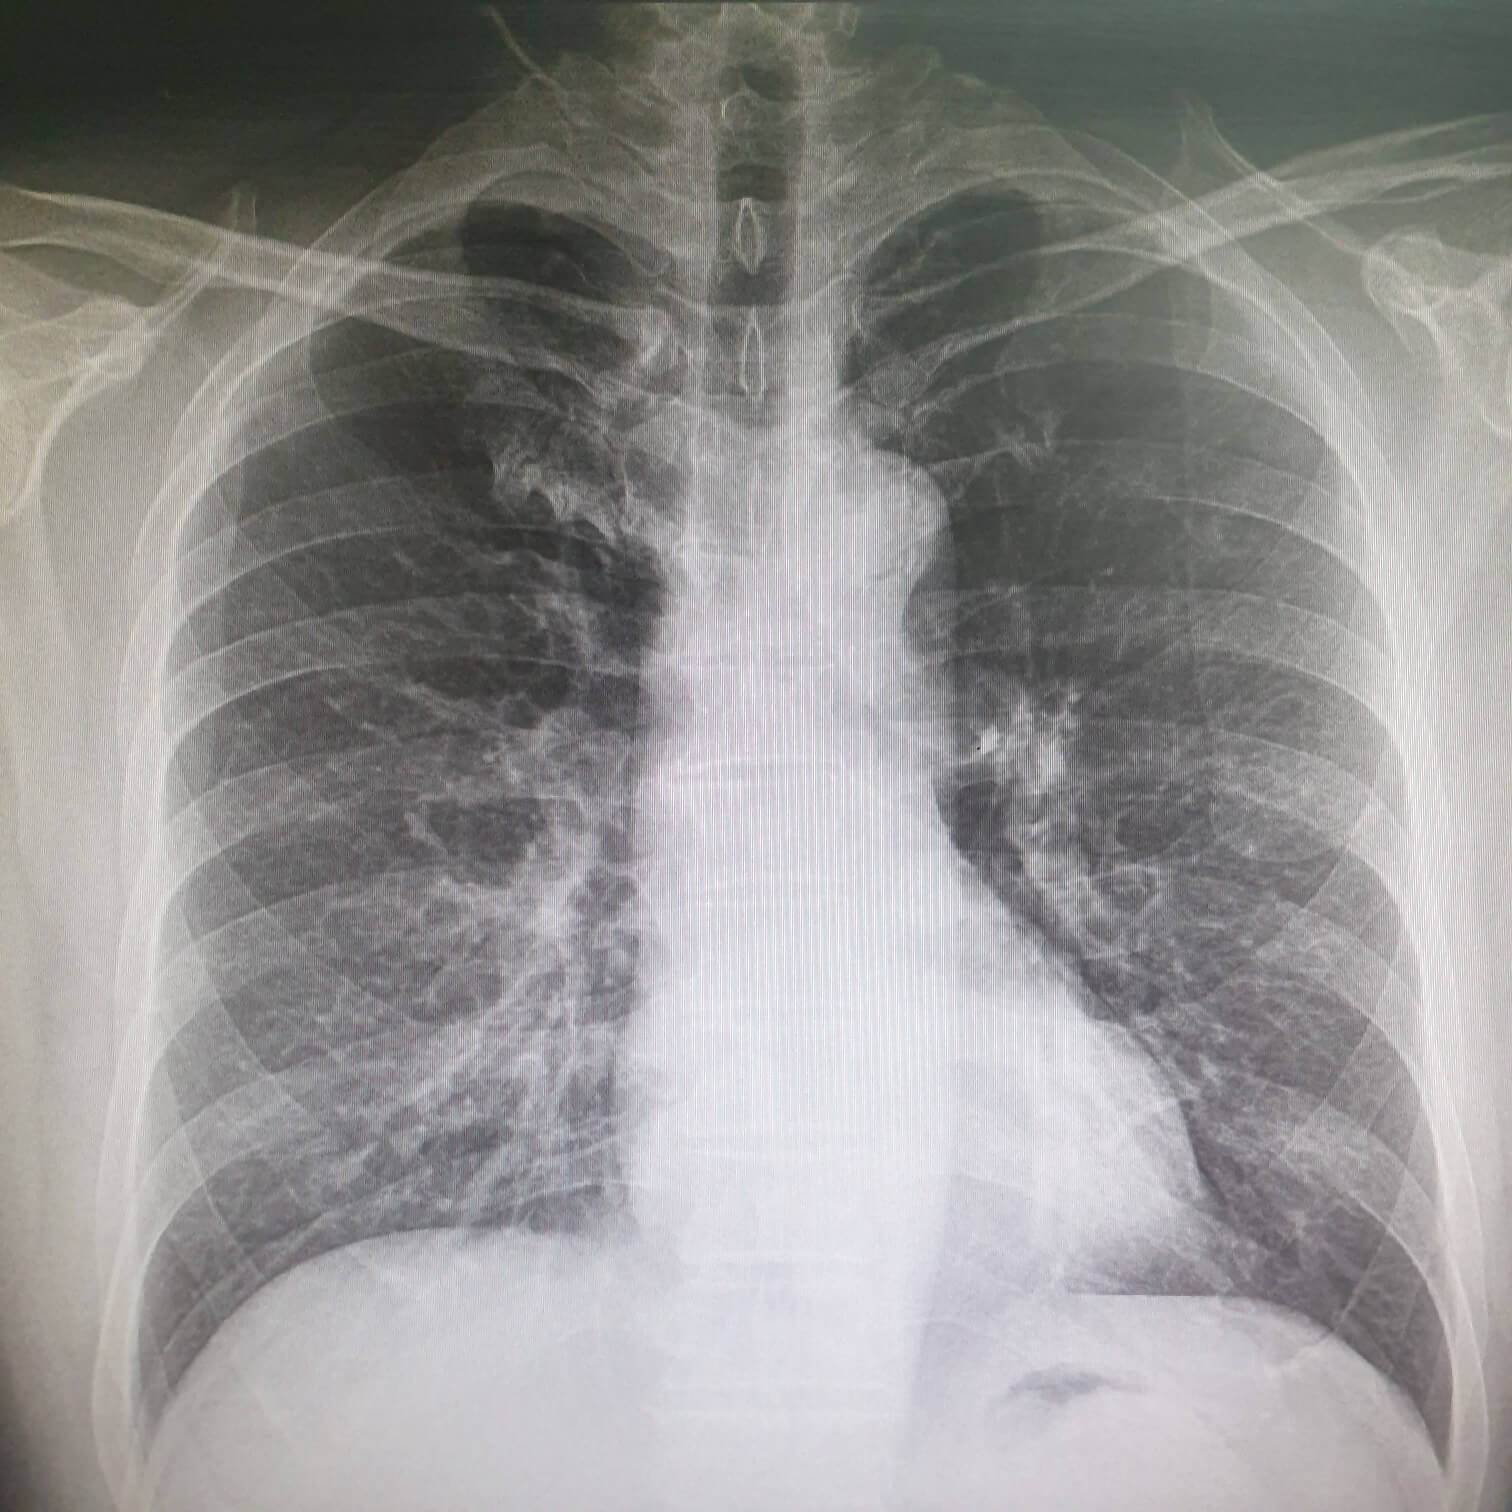

| 일반건강검진 | 비만 : 신장, 체중, 허리둘레, 체질량지수 측정 시각, 청각이상 : 시력, 청력 검사 고혈압 : 혈압 측정 폐결핵, 흉부질환 : 흉부방사선촬영 (X-ray검사) 구강질환 : 구강검진 (충치등의 치과검진) |

| 중학교 1학년 | 신체계측, 혈압, 소변검사, 허리둘레 및 혈액검사(비만학생에 한함), 흉부X-선, 구강 등 |

| 고등학교 1학년 | 신체계측, 혈압, 소변검사, 허리둘레 및 혈액검사(비만학생에 한함), 혈색소(여학생), 흉부X-선, 구강 등 |